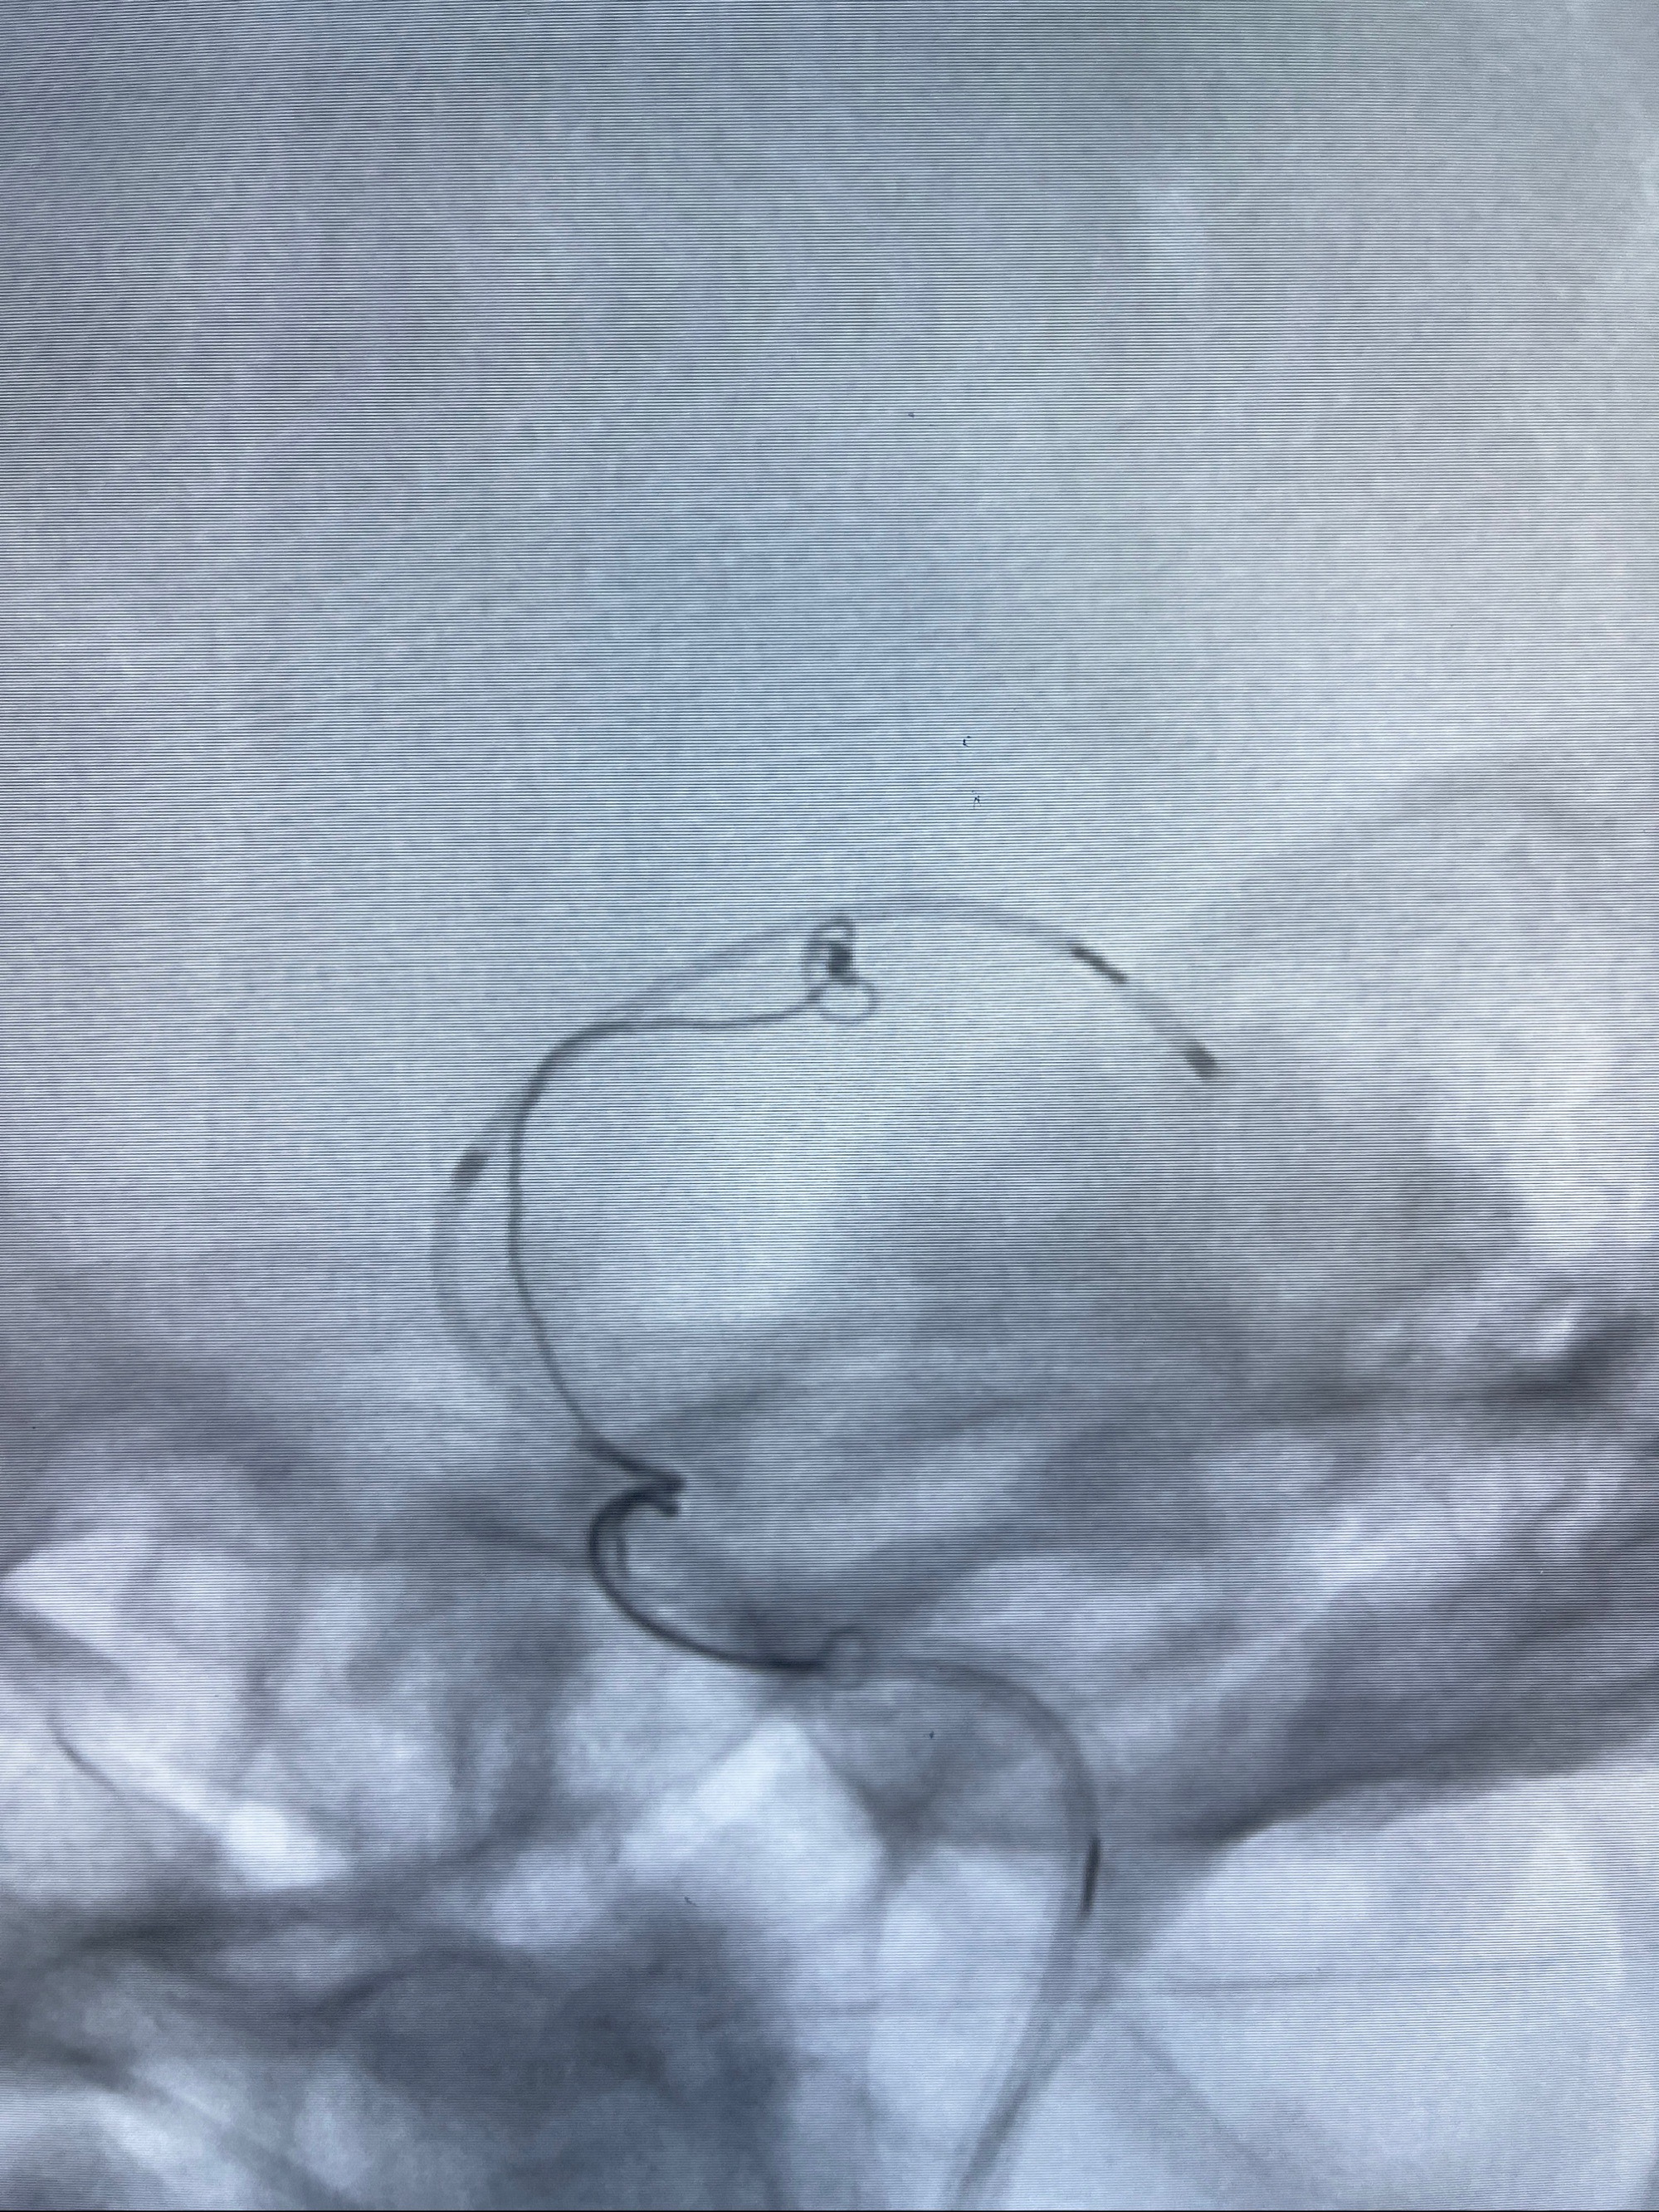

2.外科手术夹闭or介入支架辅助栓塞